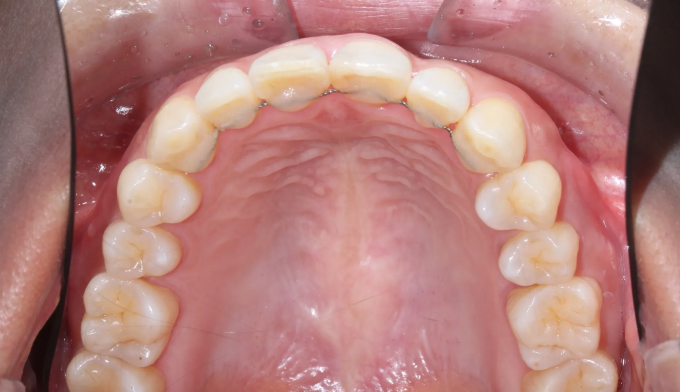

40대가 넘어가면서부터 앞니들이 점점 가운데로 몰리고 삐뚤빼뚤해지는 경우가 많습니다.

우리의 이들은 어릴적 맹출한 위치에 평생 있지 않고, 긴 시간에 걸쳐서 앞쪽으로 쏠리기 때문입니다.

삐뚤빼뚤한 정도가 심하지 않다면 간단한 앞니 부분교정만으로 충분히 배열이 가능하지만, 확보해야할 공간이 크다면 전체교정을 통해 어금니를 뒤로 보내야 앞니를 배열할 수 있는 공간을 만들 수 있습니다.

총 치료기간은 14개월 소요되었습니다.